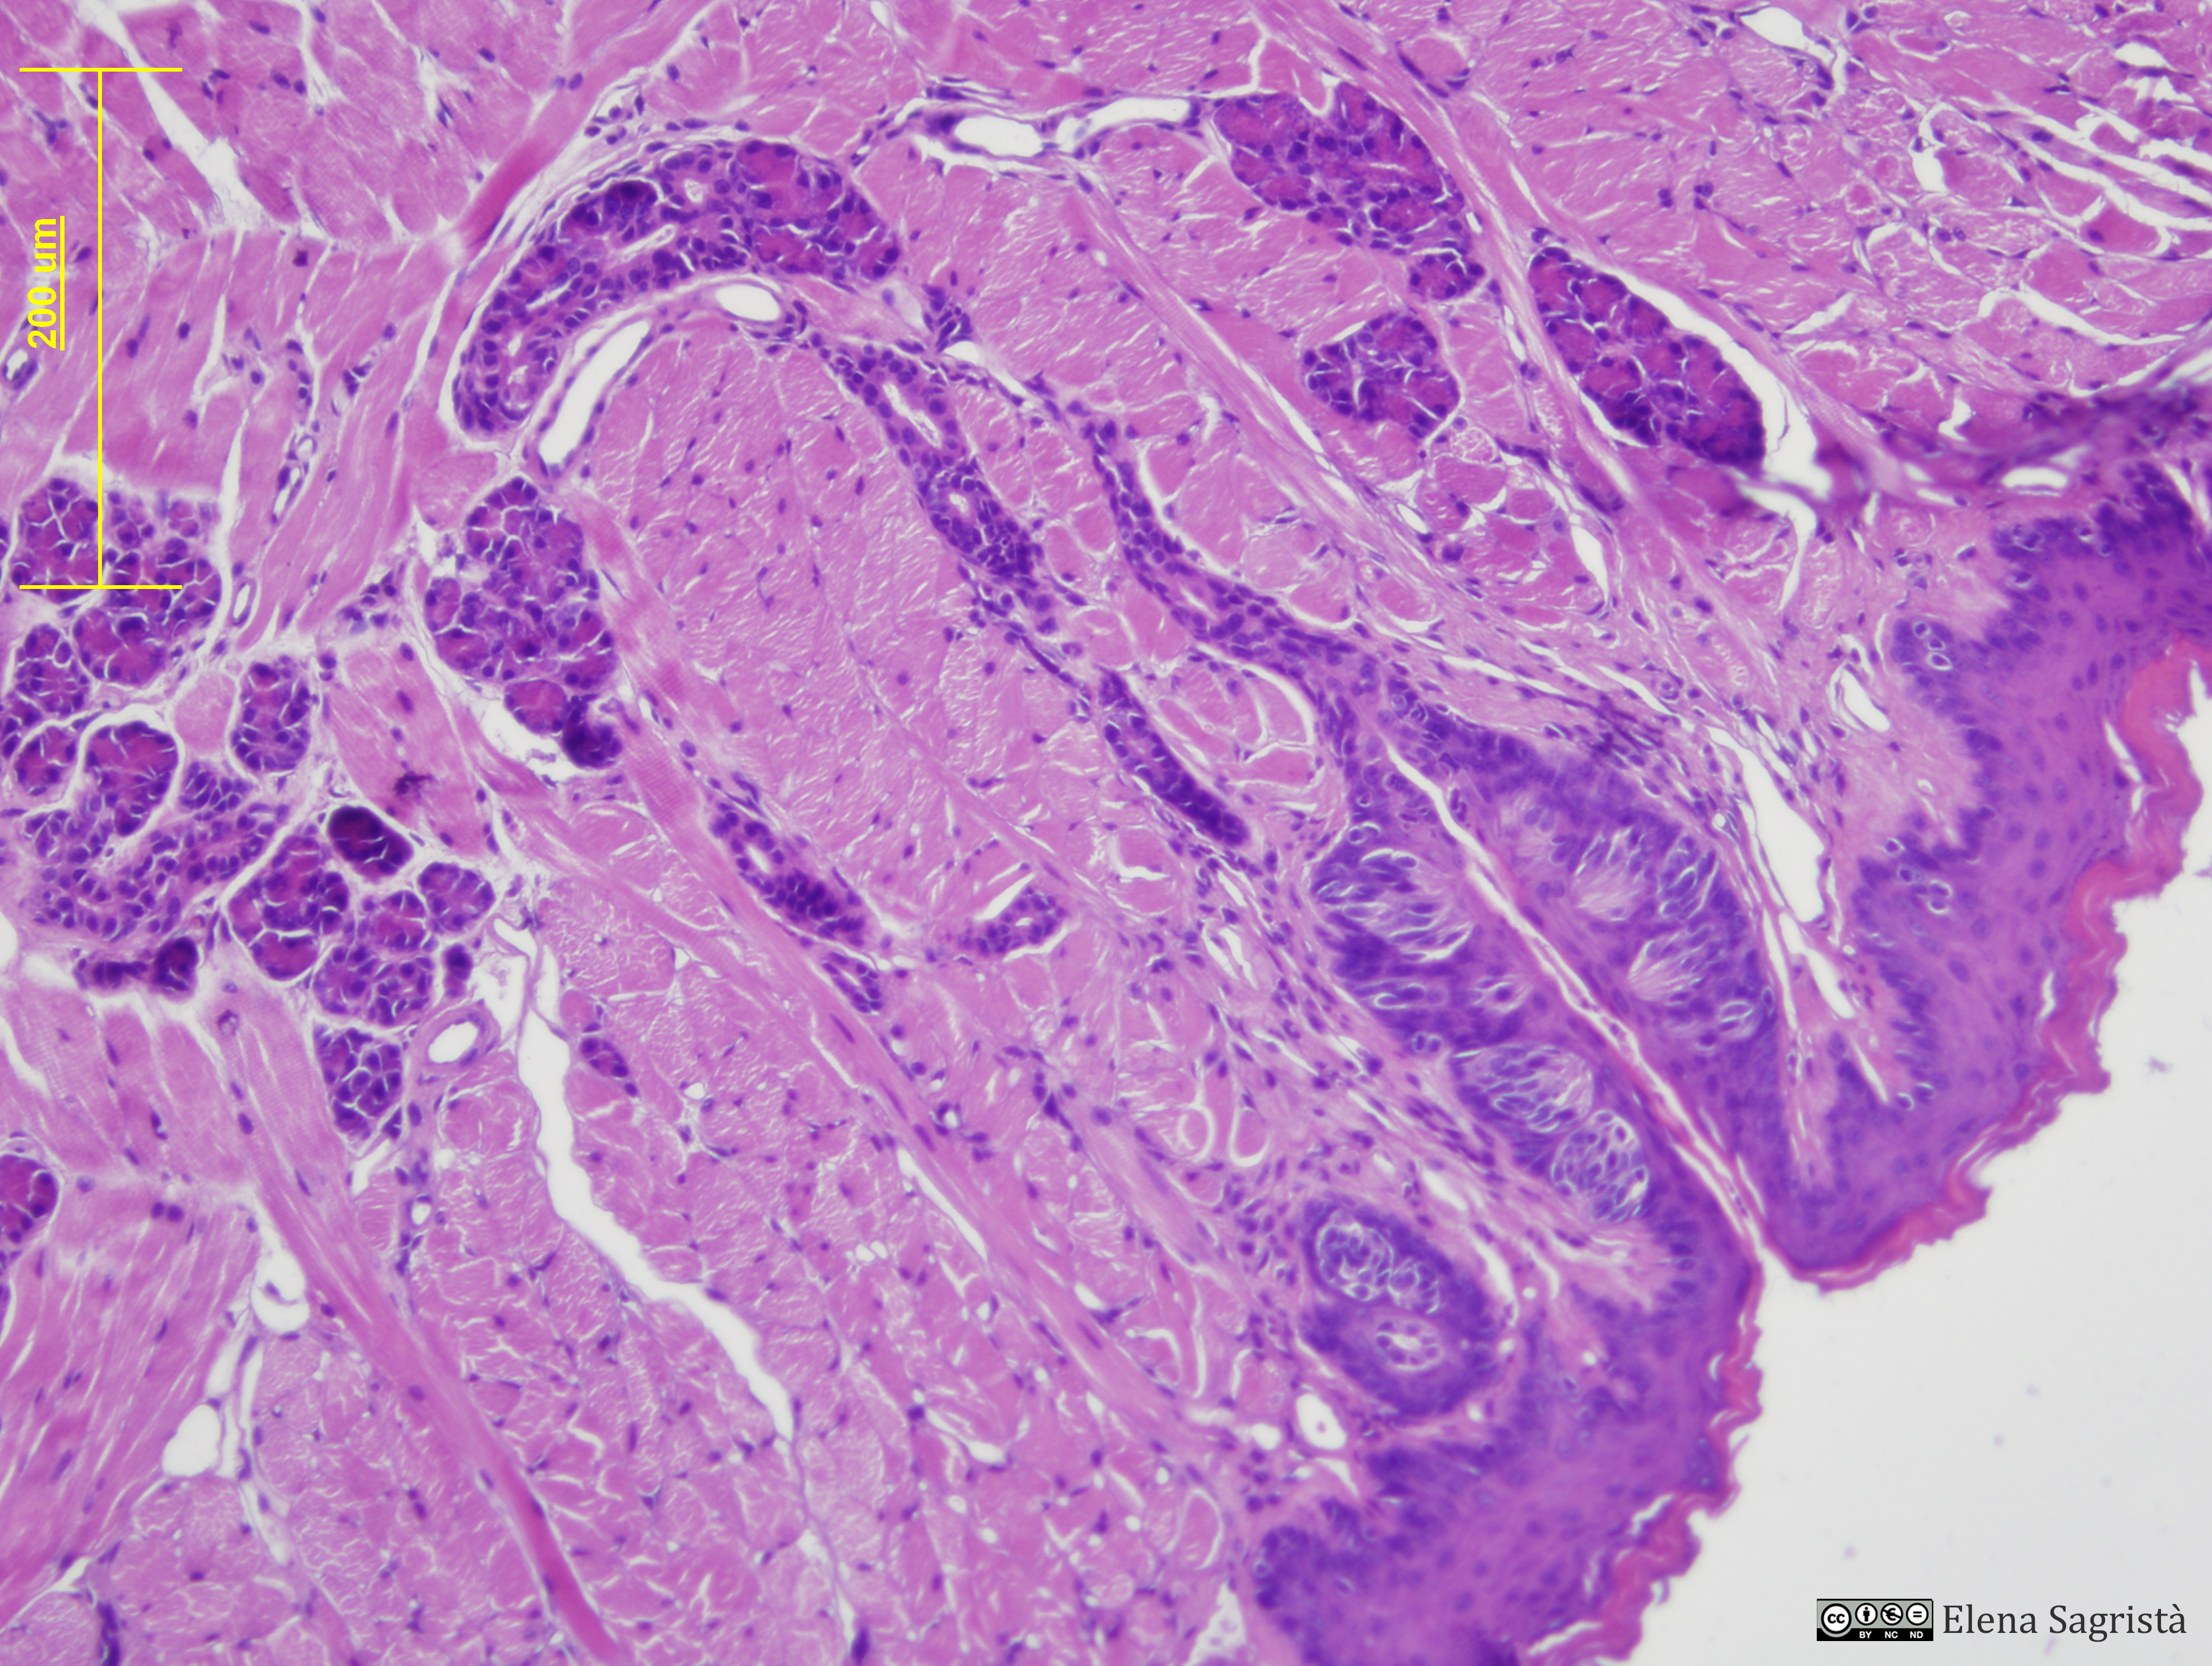

Histologia imatges: 14 Llengua

Imatges de preparacions histològiques de Llengua. Microscopia òptica.